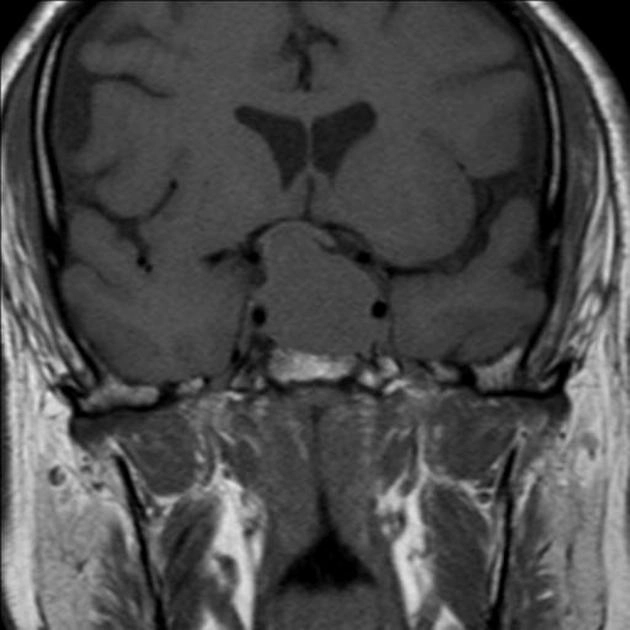

• Đột quỵ tuyến yên (Pituitary apoplexy)

• U sọ hầu dạng Adamantinoma (Adamantinomatous Craniopharyngioma)